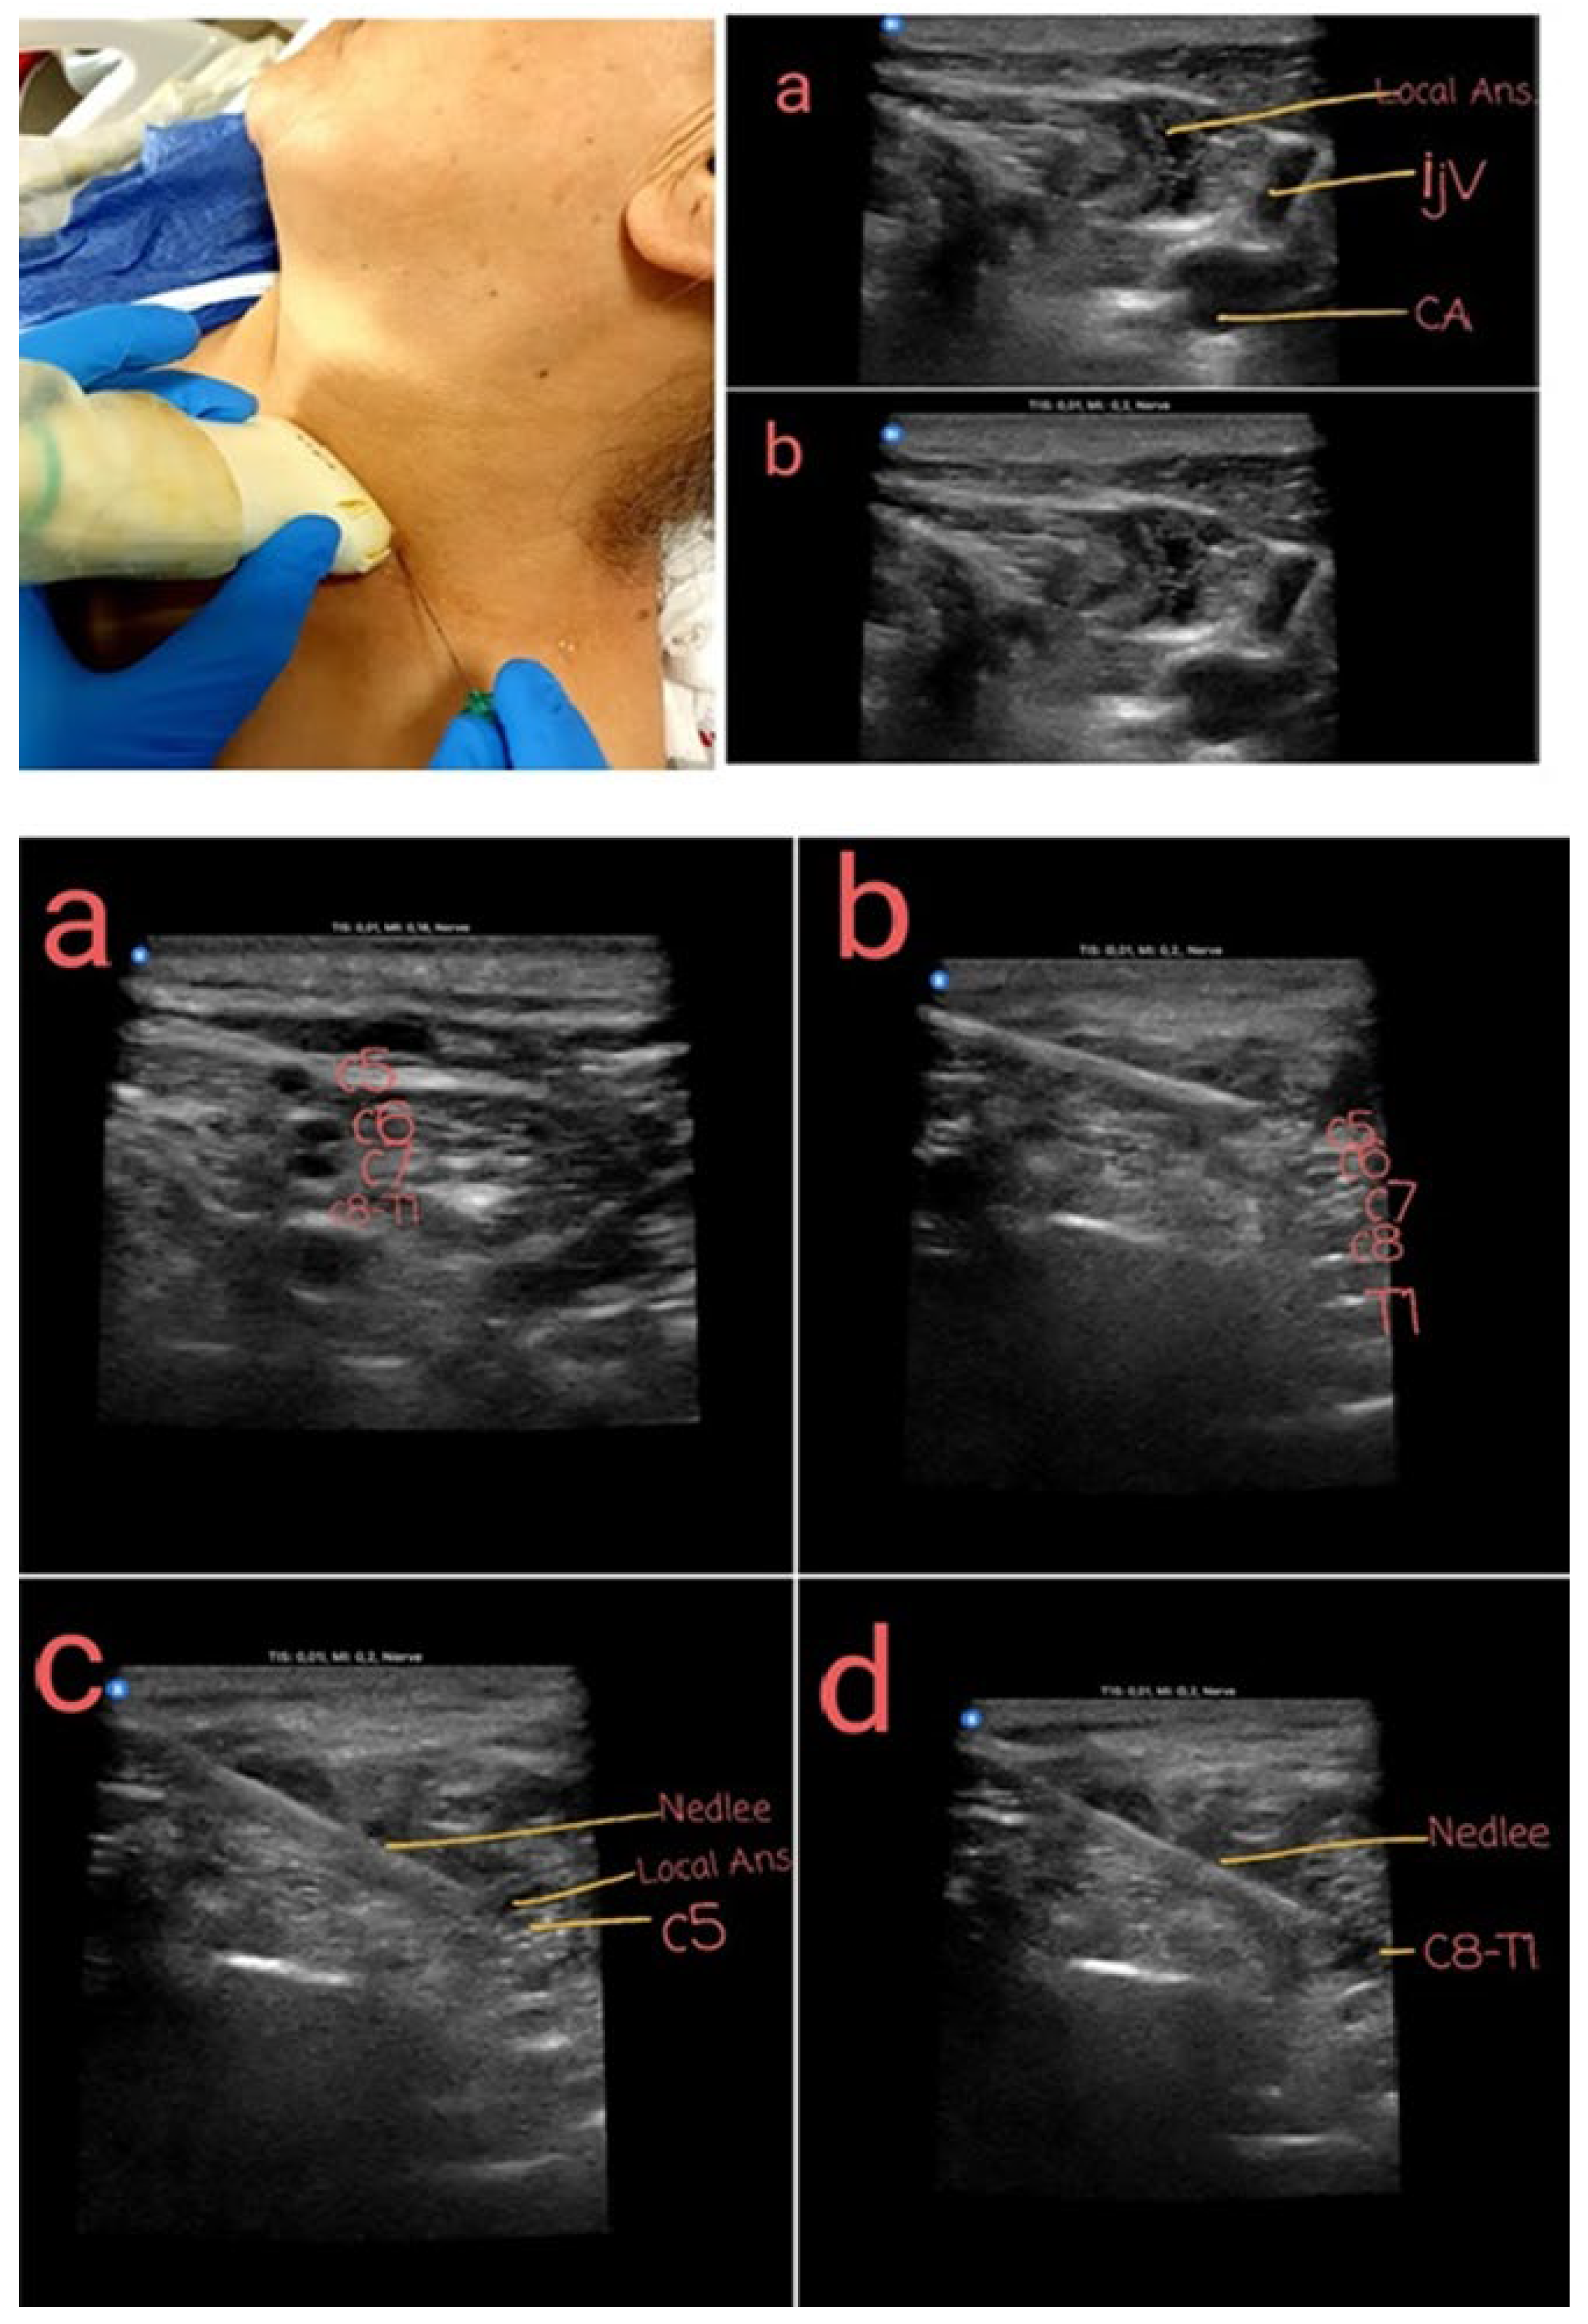

Figure 4. Superficial cervical plexus block technique IJV: Internal jugular vein CA: Carotid Artery Interscalene block with USG: Targeting and blocking the C5 and C8-T1 roots a: Interscalene nerve alignment b: Interscalene nerve and puncture needle c: Targeting the C5 nerve root specifically with the puncture needle d: Targeting the T1 nerve root specifically with the puncture needle.

Under ultrasound guidance, a superficial cervical plexus block (SCPB) was performed by imaging at the midpoint of the sternocleidomastoid (SCM) muscle. Ten milliliters of 2% prilocaine were infiltrated beneath the SCM fascia. Similarly, an interscalene block was performed under ultrasound guidance by identifying the brachial plexus at a depth of 1–3 cm. A block needle was positioned within the tissue space between the anterior and middle scalene muscles, and local anesthetic was injected until the spread around the brachial plexus was visualized on ultrasound. In this procedure, which primarily targets the C5 and T1 nerve roots, a total of 20 ml of solution was administered, consisting of 60 mg lidocaine (2%, 3 ml) + 50 mcg fentanyl (1 ml) + 16 ml saline (SF). When the T1 root could not be visualized, a local anesthetic was applied to the distal portions of the C7 and C8 roots.